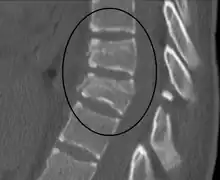

| A Chance fracture of T10 and fracture of T9 due to a seatbelt during an MVC. | |

The cause is classically a head-on motor vehicle collision in which the affected person is wearing only a lap belt.[2] Being hit in the abdomen with an object like a tree or a fall may also result in this fracture pattern.[12][10] It often involves disruption of all three columns of the vertebral body (anterior, middle, and posterior).[7][6] The most common area affected is the lower thoracic and upper lumbar spine.[6] A CT scan is recommended as part of the diagnostic work-up to detect any potential abdominal injuries.[5] The fracture is often unstable.[1]

On plain X-ray, a Chance fracture may be suspected if two spinous processes are excessively far apart.[10]

A CT scan of the chest, abdomen, and pelvis is recommended as part of the diagnostic work-up to detect any potential abdominal injuries.[5][10] MRI may also be useful.[10] The fracture is often unstable.[1]